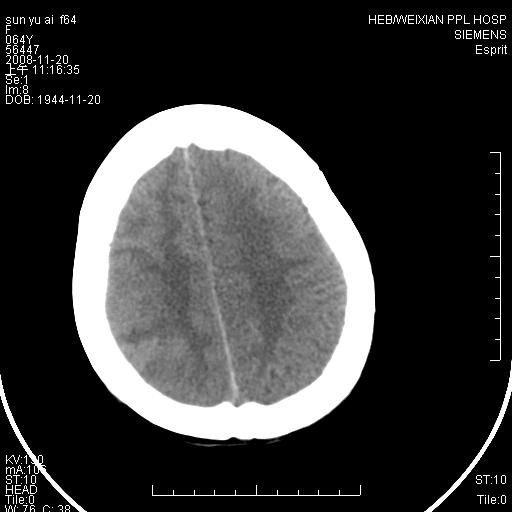

影像表现:侧脑室三角区附近可见以形态不规则的囊实性肿块,其中以囊性成分为主,实性成分为辅,边缘清晰,未见水肿,轻度占位效应,脉络丛钙化向内上移位,右侧脑室轻度扩大(也许体位所致),

1、右侧大脑半球囊实性占位病变,以囊性变为主,实性部分位于病变外后侧,周围无明显水肿,占位征象明显。

2、多考虑胶质瘤可能性大。